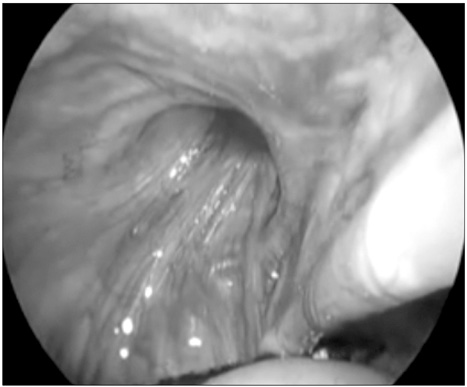

Fig. 1

View of vas and spermatic vessel.

Fig. 1 View of vas and spermatic vessel.